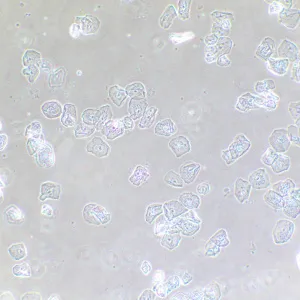

Фазово-контрастное устройство MAGUS SPH2 – это набор аксессуаров, которые позволяют реализовать на микроскопе MAGUS метод фазово-контрастной микроскопии. Фазовый контраст применяют для изучения прозрачных объектов, слабо различимых в светлом поле. Этот метод не требует окрашивания, повреждающего структуру живых образцов, поэтому подходит для широкого круга медицинских и фармакологических исследований.